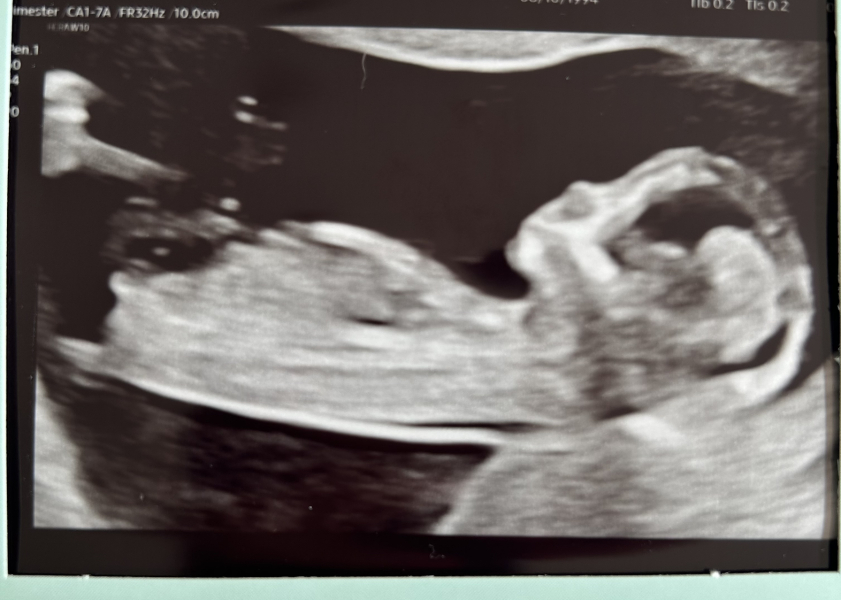

Hey all! I did post on the first oct thread and have just been reading everyone's messages since! I had my 12 week scan last week, baby was measuring ahead at 13+1. Definitely feels more real now!

What does everyone think? 💗💙

CharlieBalf · 15/04/2024 17:44

@2doggos I'd put money on a boy!

@MF94 I know it must have been frustrating but these pics are great! The one with their back to you and then upside down are hilarious and so cute. It'll be a fun story to tell when they're older.

@2doggos ahhh gorgeous baby! Look at its little ski jump nose😍I want to believe it’s a girl as that’s what my baby’s nub looks like and I legit can’t think of a boys name my partner and I both like.